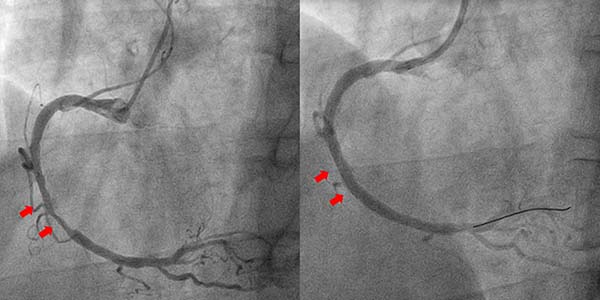

案例2

2025年6月23日凌晨,兰先生因突发胸痛由120急救车送至清华大学附属垂杨柳医院急诊,心电图提示下壁导联ST段抬高,拟诊断为急性下壁ST段抬高型心肌梗死。然而兰先生2年前被诊断为食管恶性肿瘤,手术后经历多轮次放化疗,发病2天前刚刚结束最后1次化疗。消化道肿瘤及放化疗增加了消化道出血风险。然而时间就是心肌,面对缺血和出血同样高危的患者,心内科胸痛绿色通道团队讨论后决定优先考虑开通梗死相关血管,自患者进入清华大学附属垂杨柳医院大门仅用时68分钟即开通患者右冠脉闭塞病变,因患者急诊术中冠脉血栓负荷重,行血栓抽吸及球囊扩张后,经强化抗栓治疗1周,择期于右冠脉病变处置入新型药物涂层支架。术后一个月,将双抗改为单抗,降低了消化道出血风险。